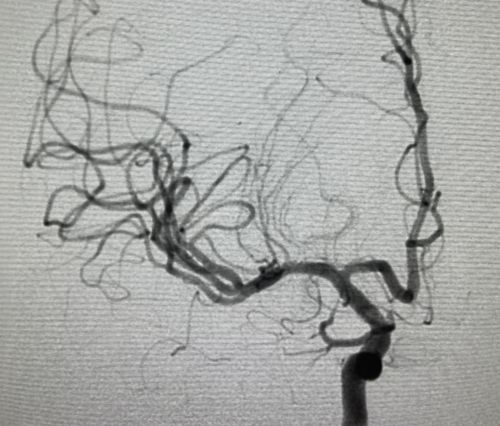

血栓堵塞大脑中动脉。

省医介入血管外科刘放其副主任医师等为患者进行脑血管造影及取栓手术。